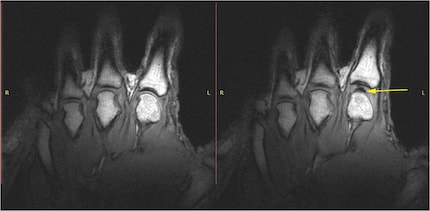

Das Knackgeräusch entsteht also nicht, weil du dein Gelenk ausrenkst oder die Knochen brichst. Es ist das Geräusch der winzigen Gasbläschen, die sich gerade bilden. Das haben kanadische Forschende 2015 mit hochauflösenden MRT-Videos bewiesen – live beim Knacken gefilmt.